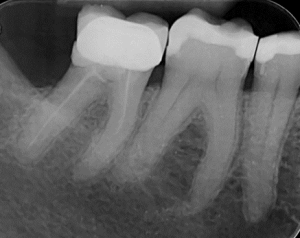

Clinical Cases